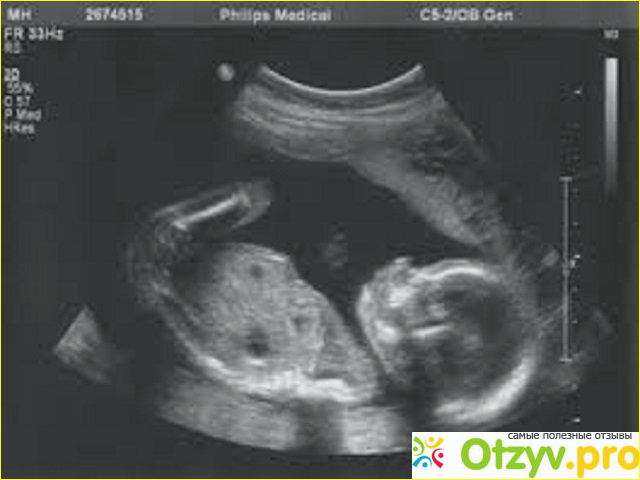

Обзор: СКРИНИНГ отзывы - развод или правда? Определение групп риска

Повод понервничать. СКРИНИНГ отзывы - развод или правда?

Лучшее средство от перхоти - гильотина! Так кратко характеризуются скрининги. Суть такова, что на раннем этапе беременности выявляют "рисковых" детей. А дальше, после еще нескольких анализов, если таки пороки развития подтверждаются - выход только один.